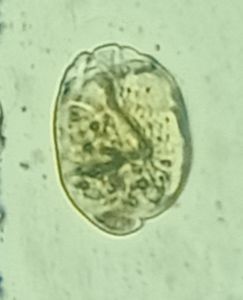

I am Dr.S.Meignanalakshmi, working as Professor, at the Directorate of Centre for Animal Health Studies, TANUVAS, Chennai-51. Working on Foldscope project on "Foldscope for diagnosis of Rumen Acidosis and parasitic infections in cattle" sanctioned by DBT